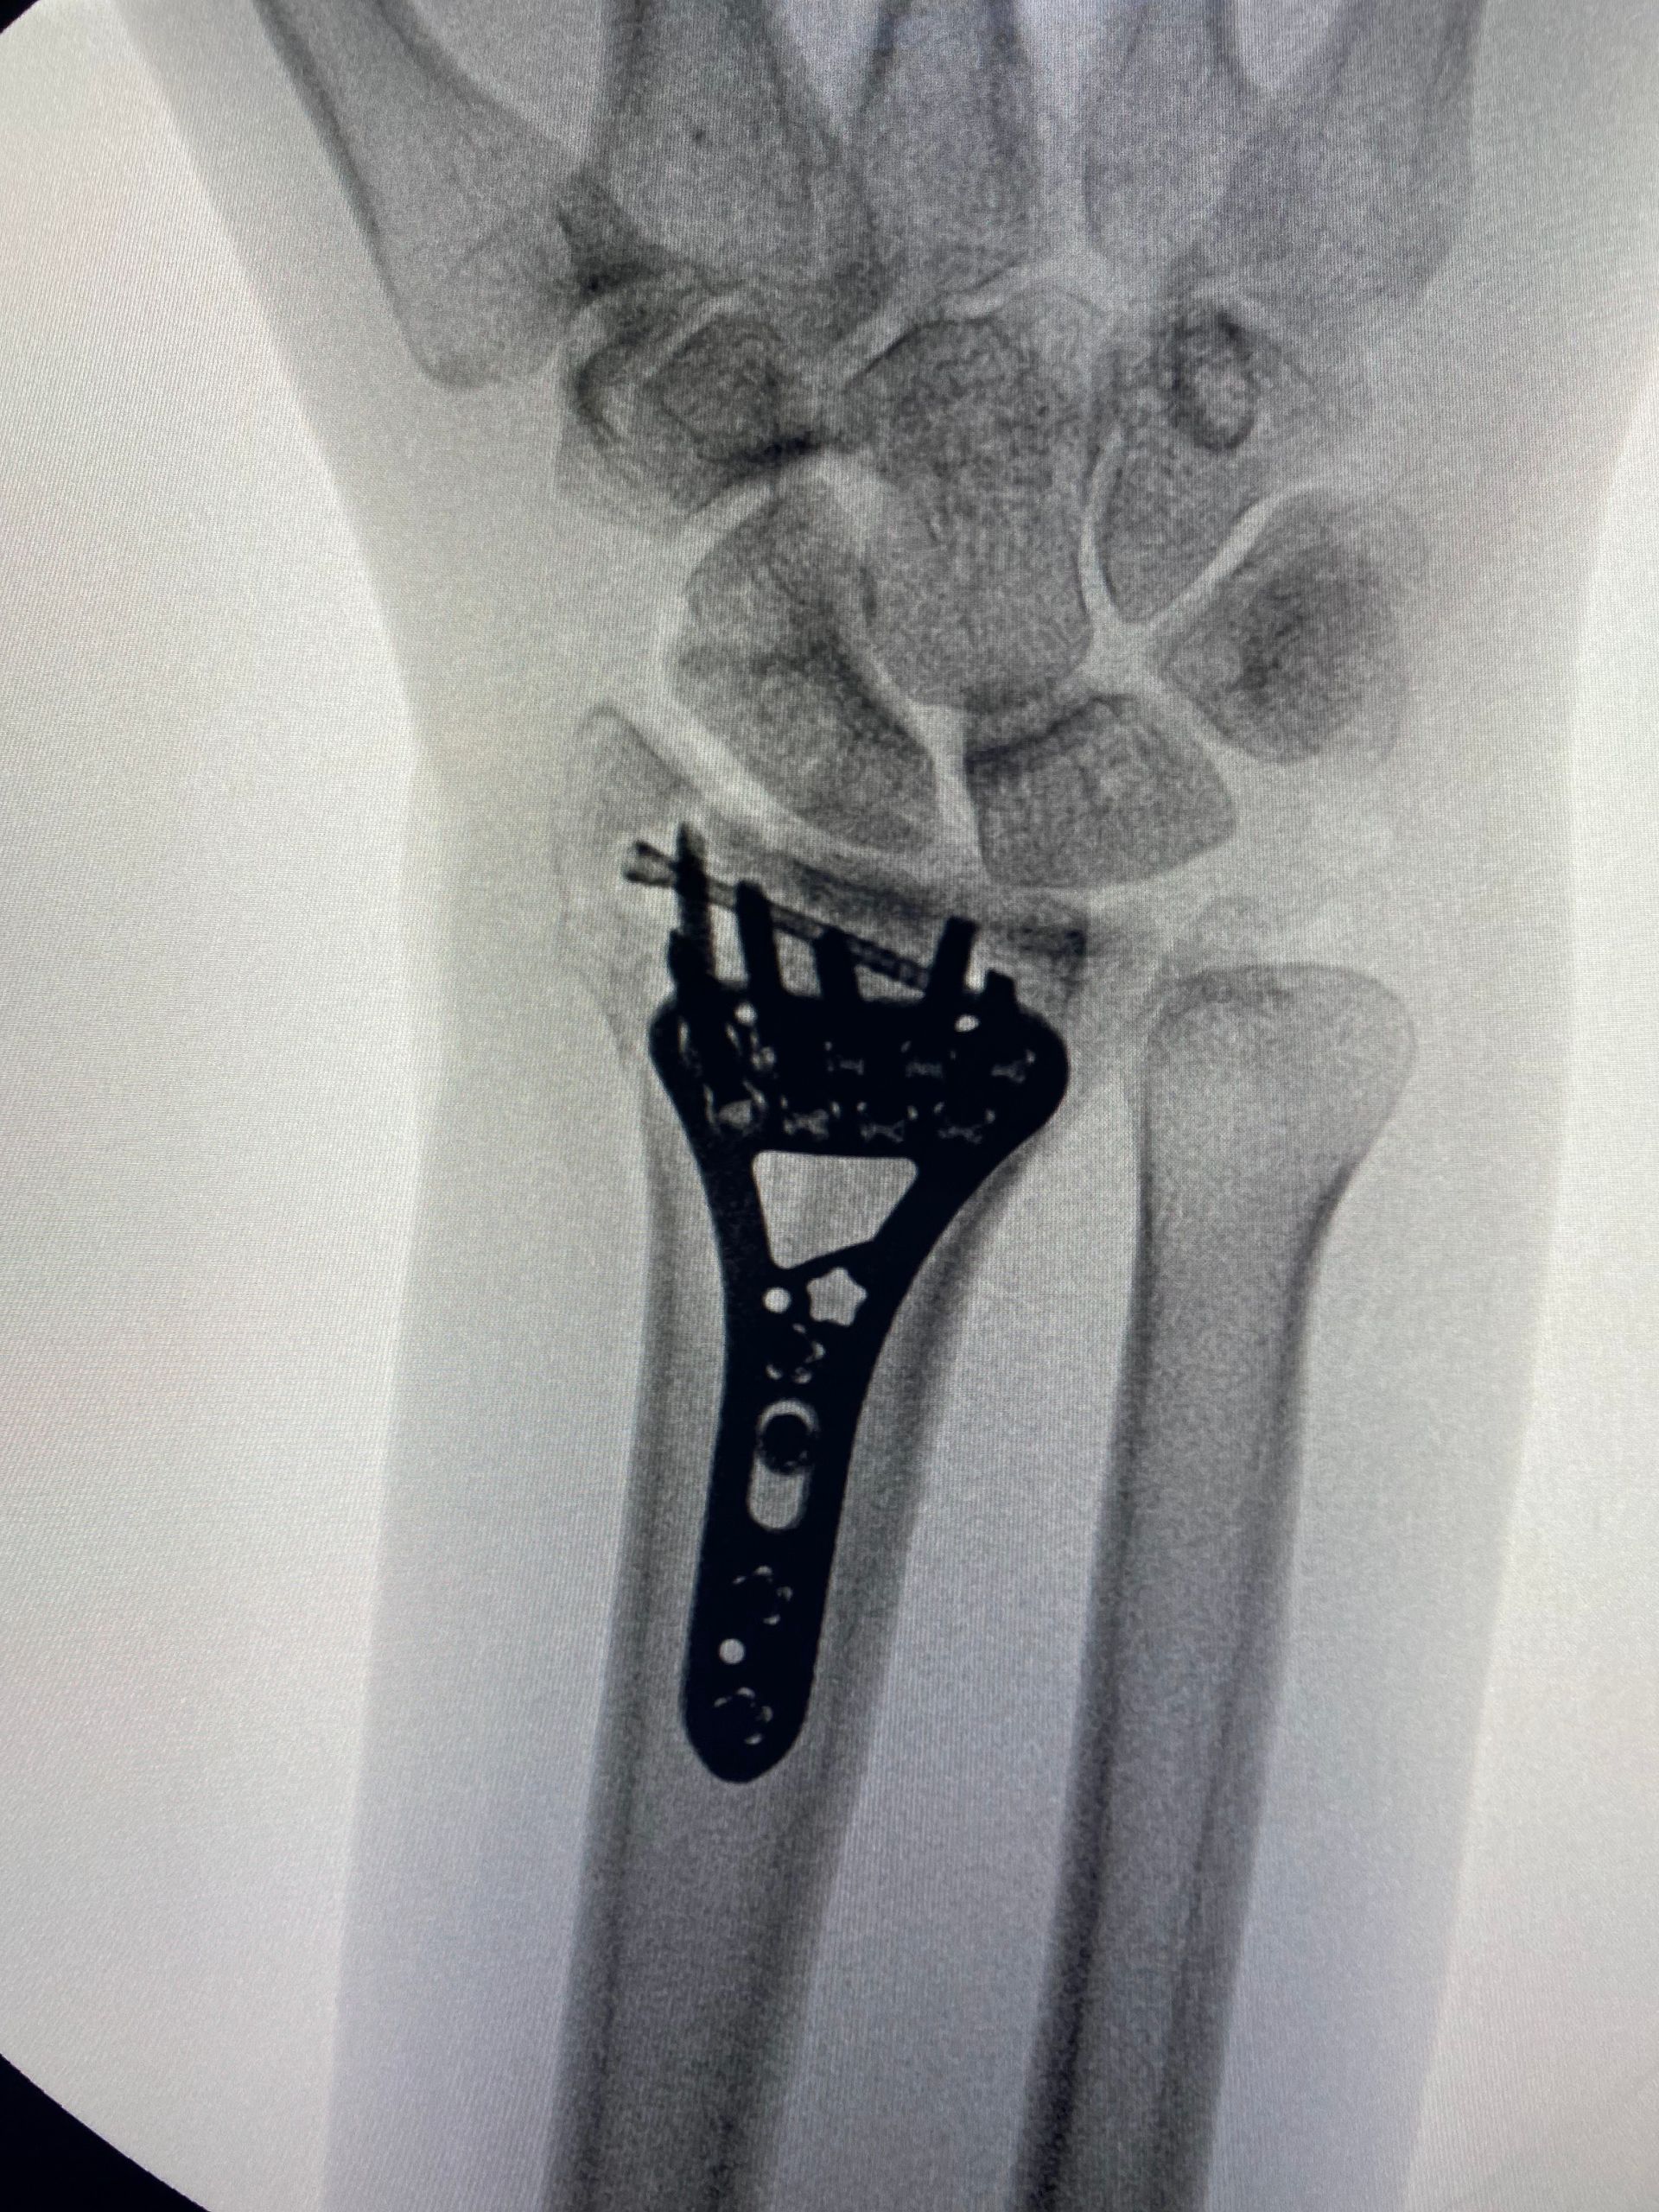

Fernandez tipo III - Fraturas compressivas articulares

- As fraturas tipo "die-punch" são causadas por um trauma axial que causa uma depressão da superfície articular, geralmente na coluna intermediária;

- A redução da fratura de modo preciso está indicada para obtermos resultados ótimos;

- A gravidade da fratura intra articular pode ser difícil de julgar somente pela radiografia, havendo indicação da tomografia computadorizada.

Sequência de imagens na avaliação inicial, radioscopia intra operatória antes da cirurgia, durante a manobra de redução com utilização de um "Freer" e após a fixação da fratura (osteossíntese). A estratégia cirúrgica utilizada envolveu, além da placa e parafusos, o uso de um parafuso canulado introduzido pela borda radial do punho, cuja função foi sustentar o fragmento articular.